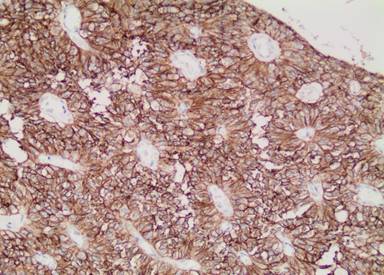

Figure 4. Tumor cells showing immunopositivity for vimentin. |

The pathological investigation showed a 13x12x11 cm pancreatic tumor, demarcated by a fibrous capsule and partial infiltration of fat tissue. Gross pathomorphology of the cut surface showed an inhomogeneous solid appearance with areas of bleeding and extensive calcifications. Microscopically, characteristic pseudopapillary formations were frequently observed (Figure 3). Pseudopapillae were formed when neoplastic cells drop away, leaving a variable number of cells surrounding delicate capillary-sized blood vessels. Immunohistochemistry was uniformly positive for vimentin (Figure 4) and CD 56 (Figure 5). Focal reactivity was detected for synaptophysin while negative reactions were found for chromogranin, neuron-specific enolase, CD10 and progesterone receptors. Proliferation index of Ki-67 was 1-2%. On the basis of these characteristic morphologic and immunohistochemical findings, the diagnosis of locally invasive solid pseudopapillary tumor of the pancreas was made. The pathologic investigation showed positive pancreatic resection margin for the tumor. For that reason re-resection of the pancreas was decided on a second look surgery. On April 2012 laparotomy was done and near total pancreatectomy was performed. The pathologic investigation for the second specimen showed negative pancreatic resection margin for tumor.